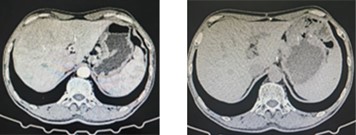

左图为喉癌治疗前,右图为喉癌治疗后

左图为胃癌治疗前,右图为胃癌治疗后